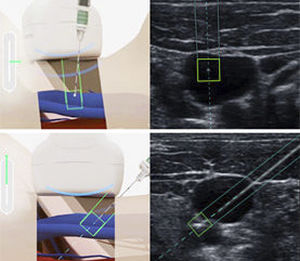

... disponible con el eZono®5000. eZGuide® permite la visualización precisa de la punta y la trayectoria de la aguja para las aplicaciones asistidas por ultrasonidos, al disponer siempre de una visualización de la posición ...